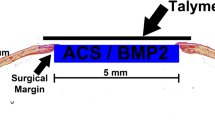

We have evaluated the capability of a collagen/poly glycolic acid (PGA) scaffold in regeneration of a calvarial bone defects in rabbits. 4 bone critical size defects (CSD) were created in the calvarial bone of each rabbit. The following 4 treatment modalities were tested (1) a collagen/PGA scaffold (0.52% w/w); (2) the collagen/PGA scaffold (0.52% w/w) seeded with adipose-derived mesenchymal stem cells (AD-MSCs, 1 × 106 cells per each defect); (3) AD-MSCs (1 × 106 cells) no scaffold material, and (4) blank control. The rabbits were then divided into 3 random groups (of 5) and the treatment outcomes were evaluated at 4, 8 and 12 weeks. New bone formation was histologically assessed. Experimental groups were analyzed by CT scan and real-time PCR. Histological analysis of bone defects treated with collagen/PGA alone exhibited significant fibrous connective tissue formation at the 12 weeks of treatments (P ≤ 0.05). There was no significant difference between collagen/PGA alone and collagen/PGA + AD-MSCs groups. The results were confirmed by CT scan data showing healing percentages of 34.20% for the collage/PGA group alone as compared to the control group and no difference with collagen/PGA containing AD-MSCs (1 × 106 cells). RT-PCR analysis also indicated no significant differences between collagen/PGA and collagen/PGA + AD-MSC groups, although both scaffold containing groups significantly express ALP and SIO rather than groups without scaffolds. Although there was no significant difference between the scaffolds containing cells with non-cellular scaffolds, our results indicated that the Collagen/PGA scaffold itself had a significant effect on wound healing as compared to the control group. Therefore, the collagen/PGA scaffold seems to be a promising candidate for research in bone regeneration.

Toosi S, Naderi‐Meshkin H, Kalalinia F, Peivandi MT, HosseinKhani H, Bahrami AR, et al. PGA‐incorporated collagen: toward a biodegradable composite scaffold for bone‐tissue engineering. J Biomed Mater Res Part A. 2016;104:2020–8.